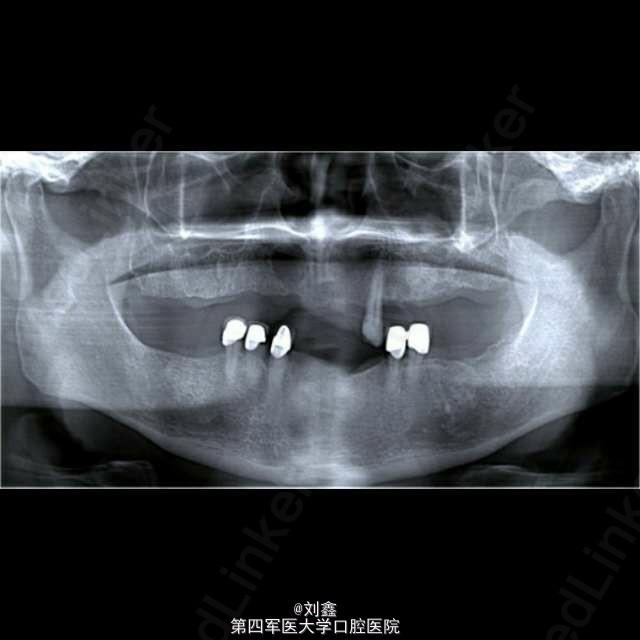

患者男, 59 岁,因曲面断层片显示上颌前部见一单房透亮影像来诊,行囊肿切除活检术,病理结果显示为表皮样囊肿。 表皮样囊肿是一种可发生在全身任何部位的良性软组织瘤样病变,男性多见,青春期前出现需考虑 Gardner 综合征。病变多局限、单个。主要病因为局部毛囊炎症,以及上皮愈合过程中毛囊漏斗部的增生及创伤性的上皮植入。影像学见单房透射影还需结合病史、检查等鉴别诊断根侧牙周囊肿、角化囊肿、球上颌囊肿、创伤性骨囊肿、成釉细胞瘤等。组织学鉴别应排除皮炎囊肿,皮样囊肿中可见皮肤附件如毛囊、皮脂腺、汗腺等。普遍认为病因包括先天性及创伤性,但有证据显示深入到颅骨等硬组织引起囊性扩张的病变多由于创伤性植入。表皮样囊肿预后良好,治疗可行保守的手术切除。